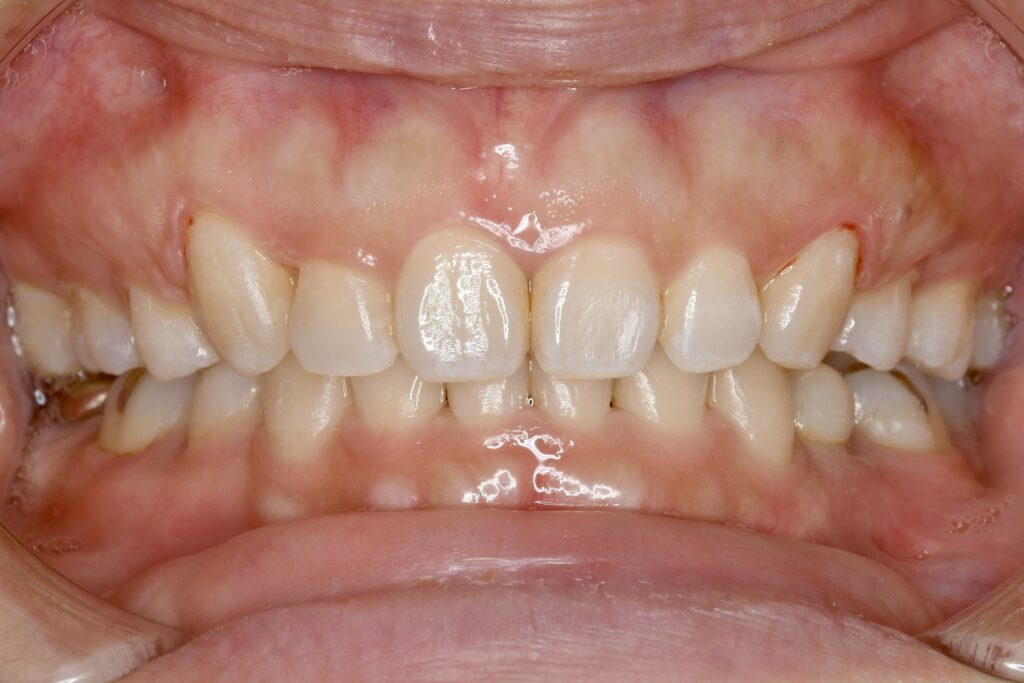

32歳 女性 治療期間:1年7ヶ月

AFTER

治療内容 上下とも歯を2本抜いて、上の前歯を後方に引きながら、でこぼこを治しました。

使用装置 マウスピース矯正装置(インビザライン)